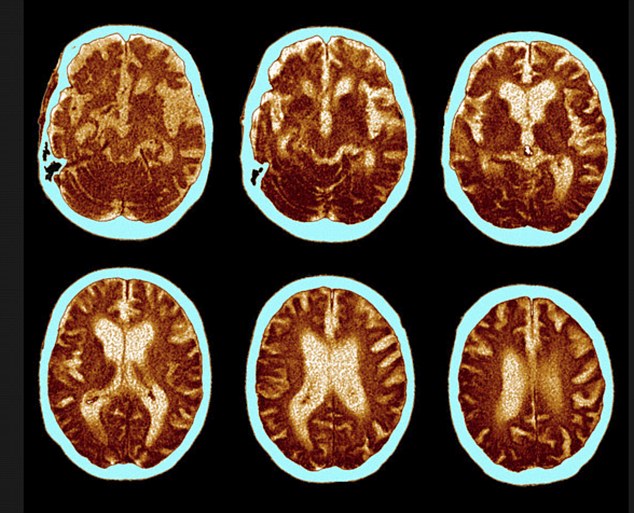

Dalam penelitian yang dipublikasikan di Journal of Neuroscience, posisi tidur menyamping atau miring diketahui lebih baik untuk kesehatan otak. Peneliti kemudian melihat hasil scan sistem pembersihan otak atau yang dikenal sebagai sistem glimfatik. Hasilnya menunjukkan, pembuangan racun di otak paling efektif terjadi saat posisi tidur menyamping dibanding tidur tengkurap maupun telentang.

Keterangan: Jalur glymphatic otak saat membersihkan limbah berbahaya, terutama ketika tidur (Dailymail)